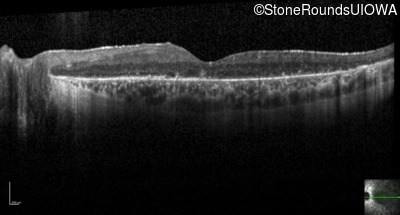

Optical Coherence Tomography - Right - 20/32 -1

Exemplar / OCT Stack

OCT Stack